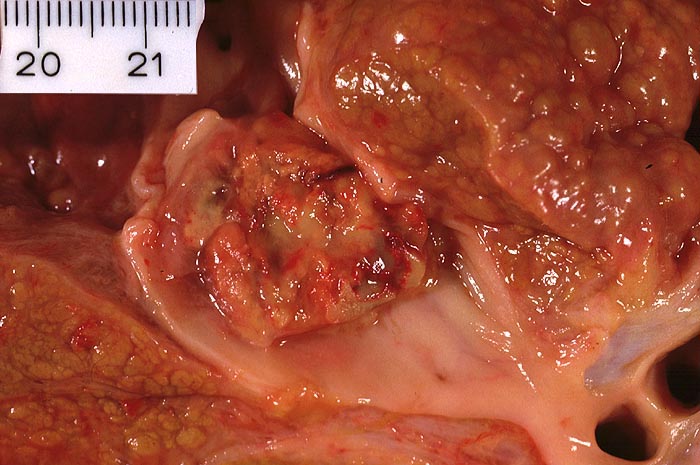

PathoPic ID 4474 - grobknotige hepatitische Leberzirrhose und hepatozelluläres Karzinom

grobknotige hepatitische Leberzirrhose und hepatozelluläres Karzinom

Grobknotiger zirrhotischer Umbau.

Tumoreinbruch in die Vena cava inferior.

Hepatitis B und C Seropositivität. St.n. Chemotherapie mit 5-FU und Hyaluronidase. St.n. mehrmaliger Chemoembolisation der Leberherde. Leberversagen.